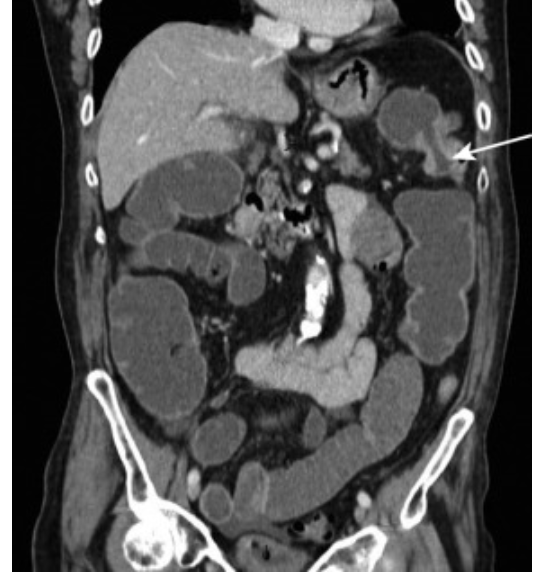

What is pictured here?